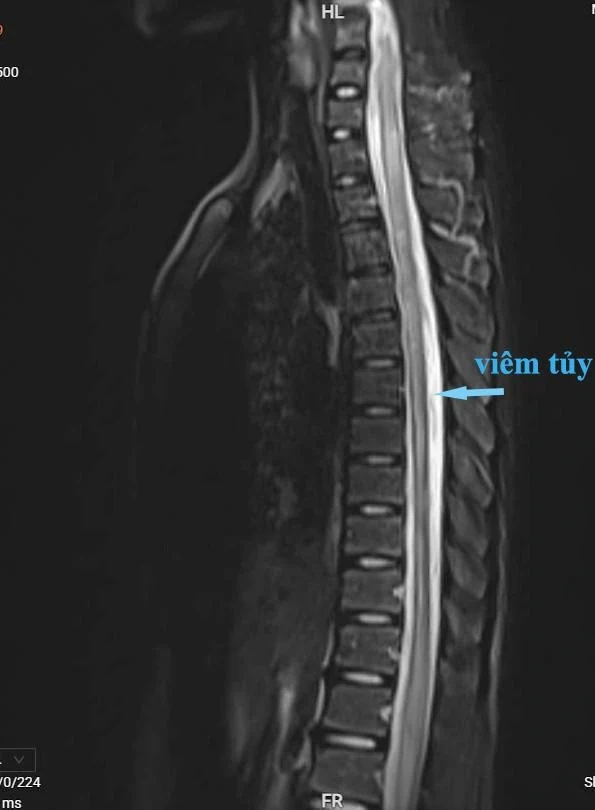

Hình ảnh phim chụp cộng hưởng từ cho thấy người bệnh bị viêm tủy từ cột sống C3 đến D7

Người bệnh nhập viện trong tình trạng tỉnh, không sốt, liệt hai chi dưới, cơ lực 2/5. Rối loạn cảm giác từ ngang mức cột sống D10 xuống hai chân, kèm theo bí tiểu. Nhận thấy tình trạng nghiêm trọng, các bác sĩ đã tiến hành chọc dịch não tủy và chụp cộng hưởng từ cột sống có thuốc, làm điện cơ, kết quả chẩn đoán xác định người bệnh mắc viêm tủy ngang từ đốt sống C3 đến D7.